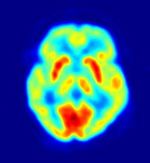

Brain imaging